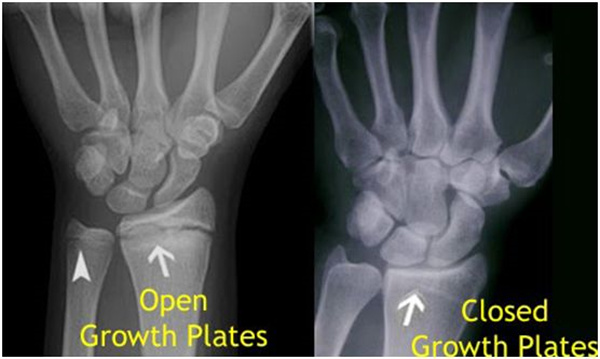

我們都知道,人體的高矮是由骨骼的生長(zhǎng)發(fā)育決定的,特別是下肢長(zhǎng)骨。長(zhǎng)骨呈長(zhǎng)管狀,在長(zhǎng)骨的兩端有一種專管骨骼生長(zhǎng)的骺軟骨,它與干骺端之間有一盤狀軟骨結(jié)構(gòu)稱為骺板(線),在幼兒的X光片上表現(xiàn)為一條較寬的透光帶。(見(jiàn)下圖)

未成年時(shí)隨著年齡的增加骺軟骨端不斷骨化,骨骼就不斷增長(zhǎng)。當(dāng)骨骺線完全閉合時(shí)骨骼就停止生長(zhǎng),個(gè)子也就不再增長(zhǎng)了。一般骨骺端完全閉合的年齡是18~20歲左右。